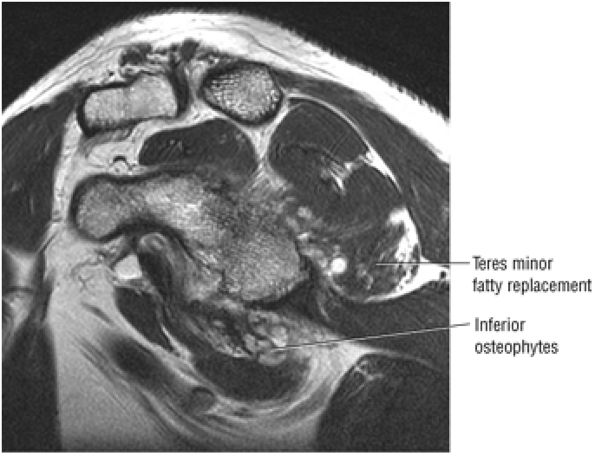

FIGURE 8.102 ● (A) The anterior undersurface of the acromion and the coracoacromial ligament form the coracoacromial arch. The subacromial subdeltoid bursa facilitates the passage of the rotator cuff and proximal humerus under the coracoacromial arch. (B) A superior axial image shows the anterior-to-posterior extent of the coracoacromial (CA) ligament perpendicular to the supraspinatus tendon. The fluid in the subacromial-subdeltoid bursa represents fluid between two serosal surfaces in contact with each other. One serosal surface is contributed by the undersurface of the coracoacromial arch and deltoid, and the other serosal surface is on the bursal side of the cuff.

|

![]() |